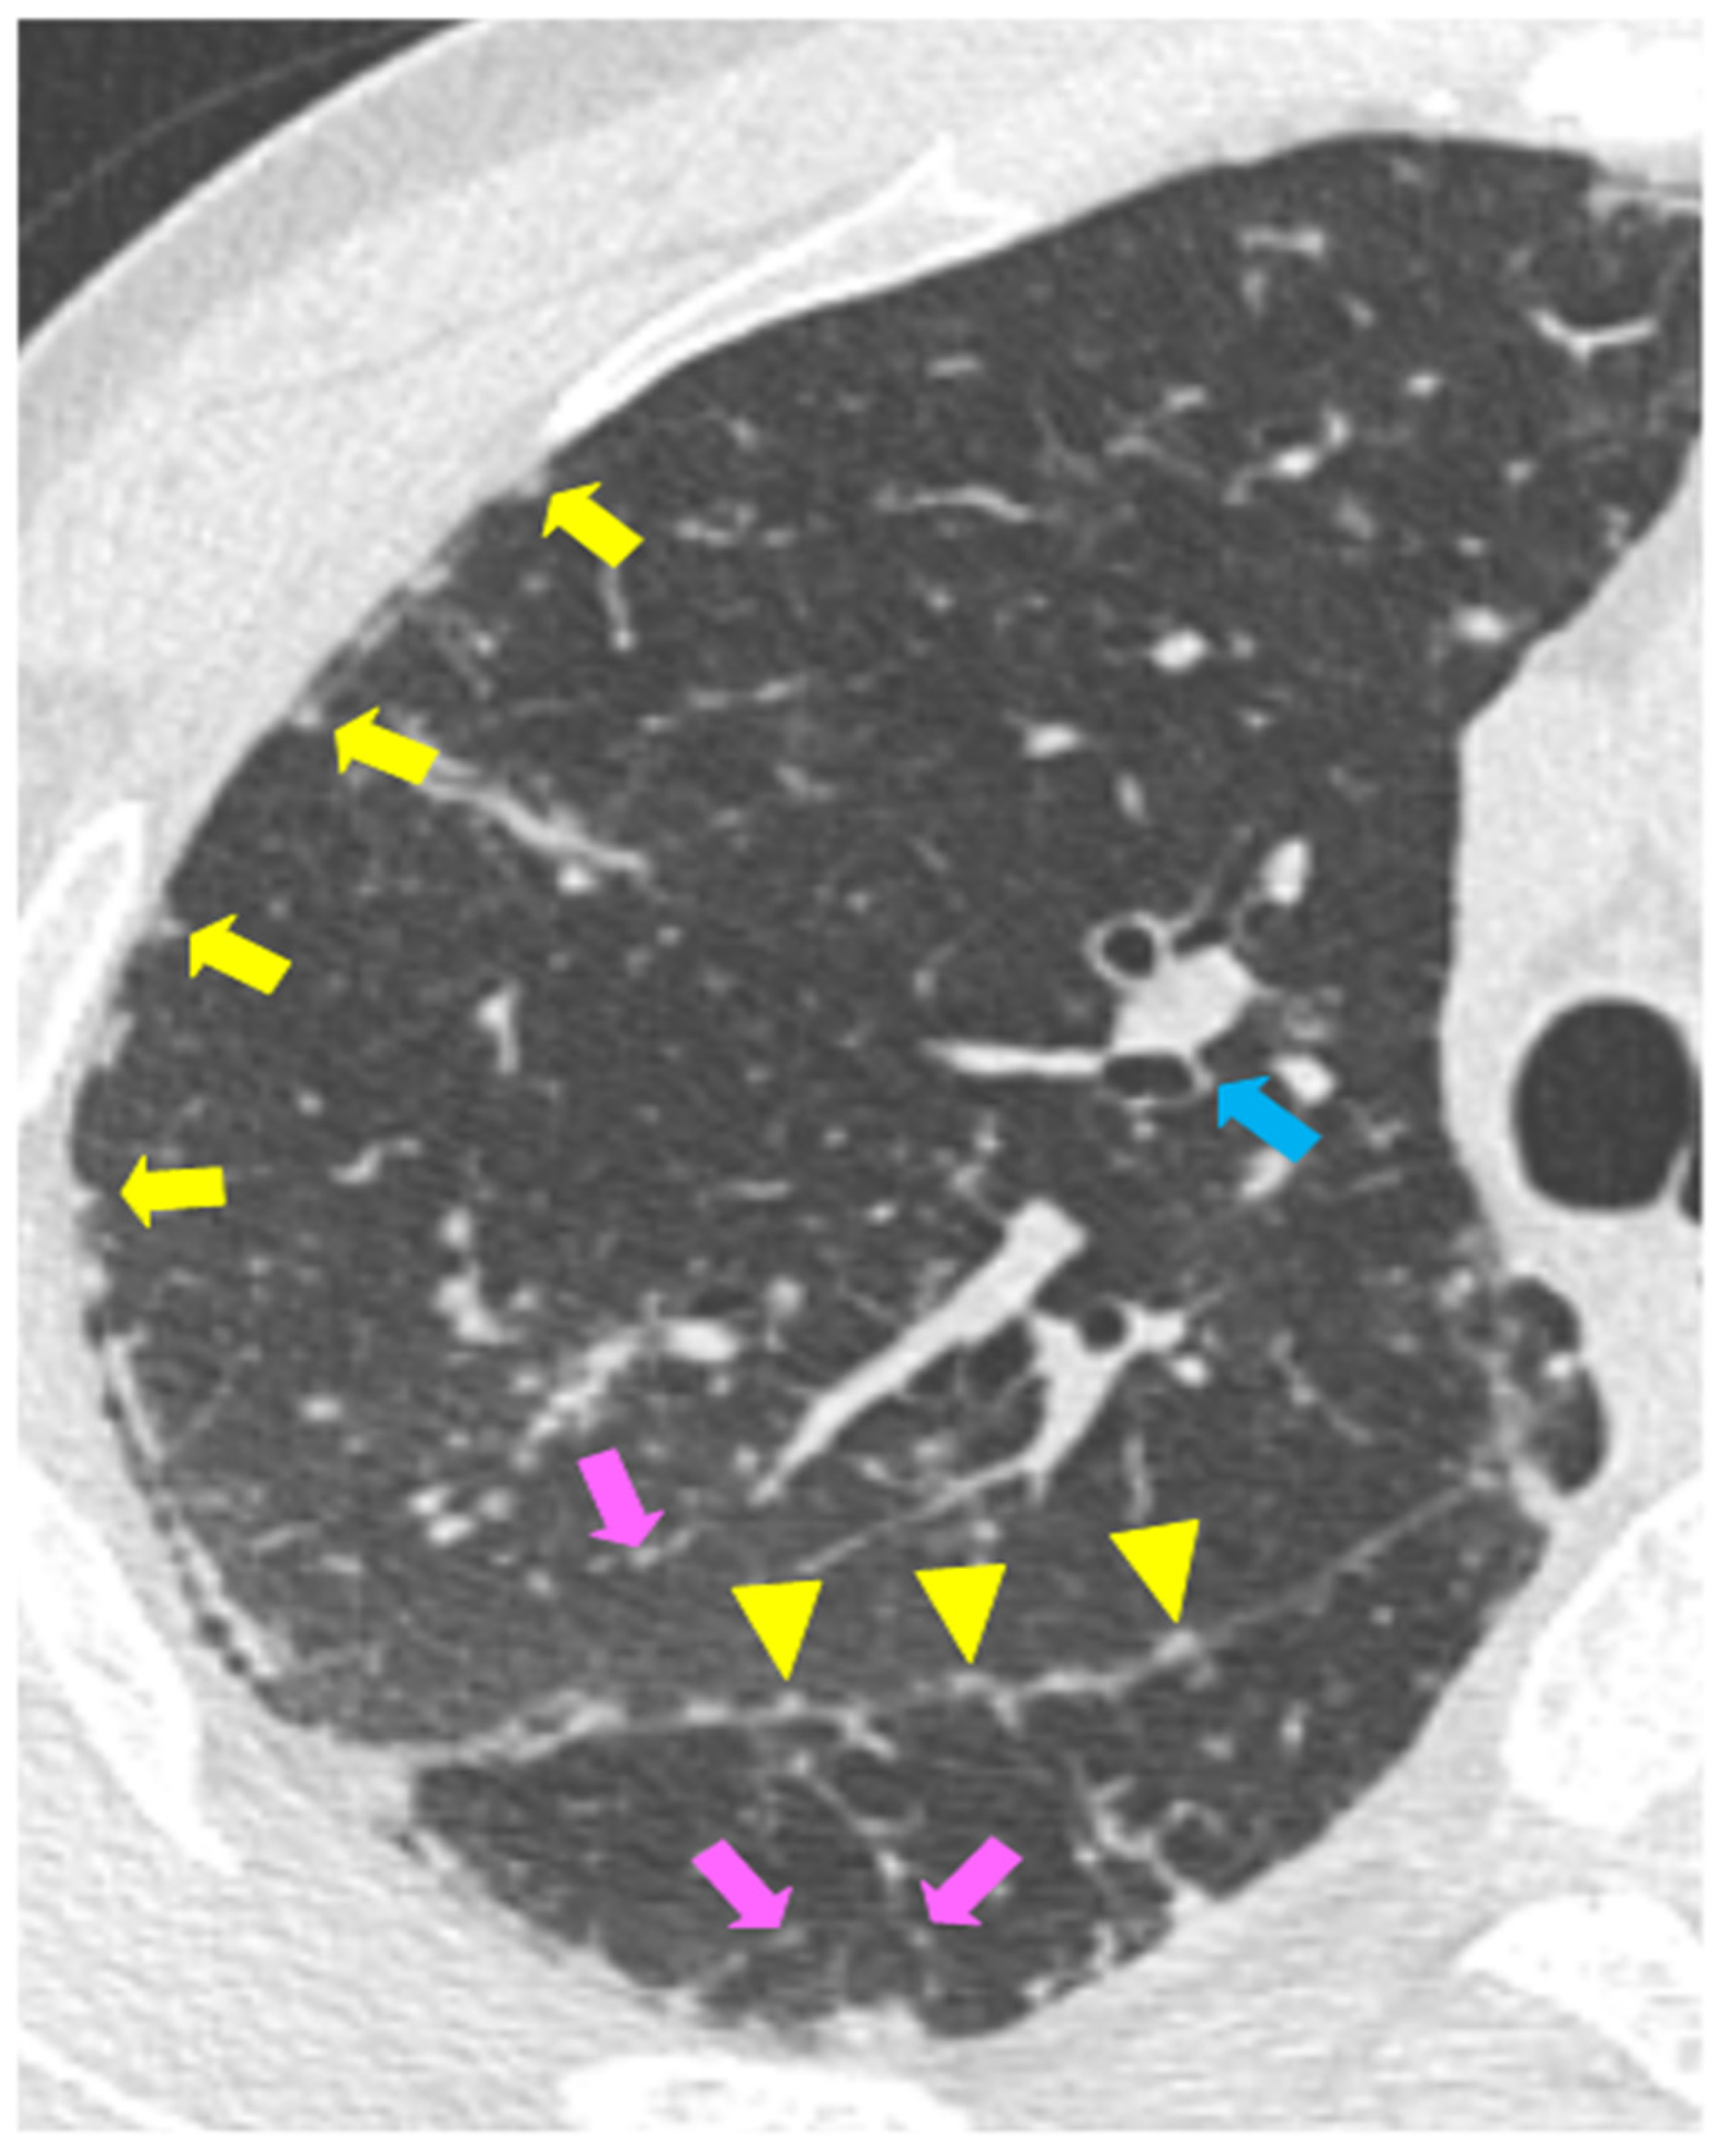

Chronic Sarcoidosis (Stage 2) on CT Scan Radiology YouTube Sarcoidosis Protein Gap Sarcoidosis is a systemic granulomatous disease which carries variable outcomes. A polyclonal increase in immunoglobulins. In this review we highlight various investigations used to diagnose sarcoidosis, outline proposed biomarkers, and discuss novel methods of sampling biomarkers. Sarcoidosis risk varies by age, sex, race, and ethnic background, leading to widely varying worldwide incidence and prevalence. (1) a compatible clinical and radiologic. Sarcoidosis Protein Gap.

JCM Free FullText Imaging of Pulmonary Sarcoidosis—A Review Sarcoidosis Protein Gap In this review we highlight various investigations used to diagnose sarcoidosis, outline proposed biomarkers, and discuss novel methods of sampling biomarkers. Diagnosis of sarcoidosis relies on three criteria: Serum protein electrophoresis is an. Sarcoidosis risk varies by age, sex, race, and ethnic background, leading to widely varying worldwide incidence and prevalence. (1) a compatible clinical and radiologic presentation, (2) pathologic. Sarcoidosis Protein Gap.